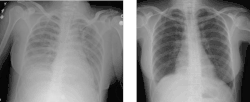

![]() Zdjęcie radiologiczne klatki piersiowej osoby z TRALI (po lewej) i po wyleczeniu (po prawej) | |

Ostre poprzetoczeniowe uszkodzenie płuc (ang. transfusion related acute lung injury, TRALI) – powikłanie występujące po przetoczeniu preparatów krwiopochodnych, polegające na ostrym, niekardiogennym obrzęku płuc. Etiologia TRALI jest nieznana; być może powikłanie spowodowane jest obecnością przeciwciał dla antygenów układu HLA lub antygenów granulocytarnych we krwi dawcy. Objawami TRALI są: nagła, silna duszność, kaszel, dreszcze, gorączka, spadek lub wzrost ciśnienia tętniczego. Śmiertelność w TRALI wynosi 6–9%[1][2]. TRALI występuje z częstością 1:2000–5000 przetoczeń[2][3]. W diagnostyce różnicowej należy uwzględnić zespół ostrej niewydolności oddechowej. W leczeniu stosuje się tlenoterapię i wentylację mechaniczną.